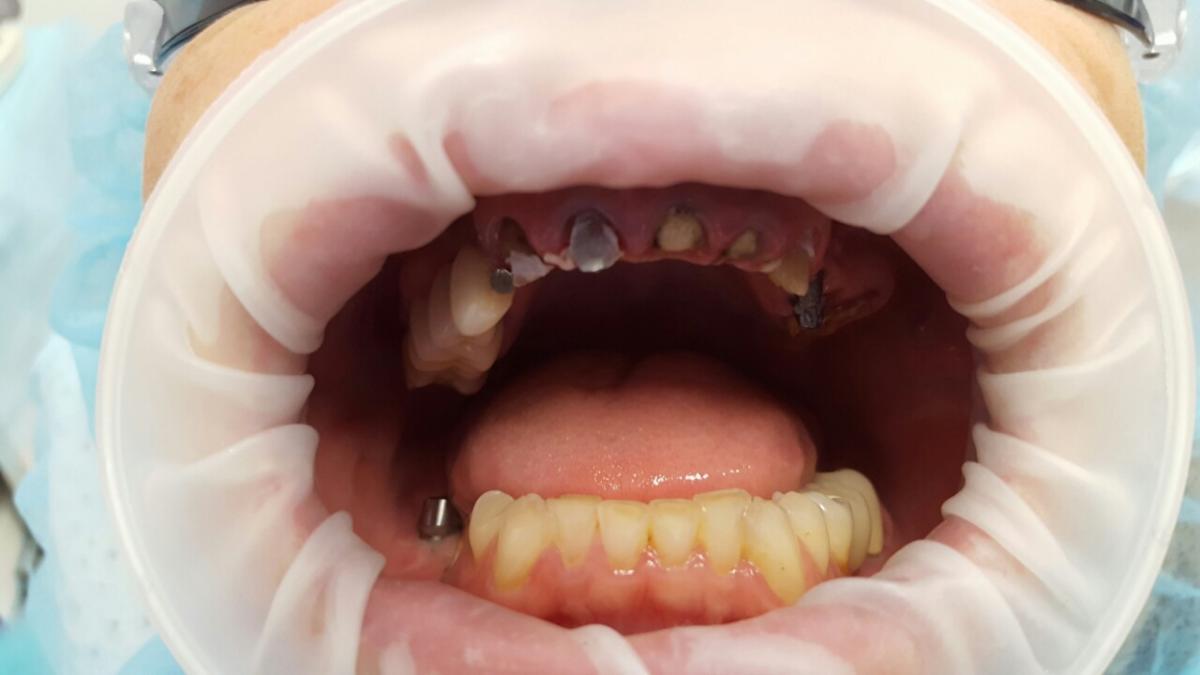

A patient case to the dental clinic with complaint connected with frond teeth defects. After the examination, he decided to provide dental treatment that includes immediate implantation of Alpha Dent implants. During the surgery he has placed 3 Alpha Dent implants in extracted teeth alveolar sockets. Then he placed allomaterial for bone regeneration over implants and sutured the wound.